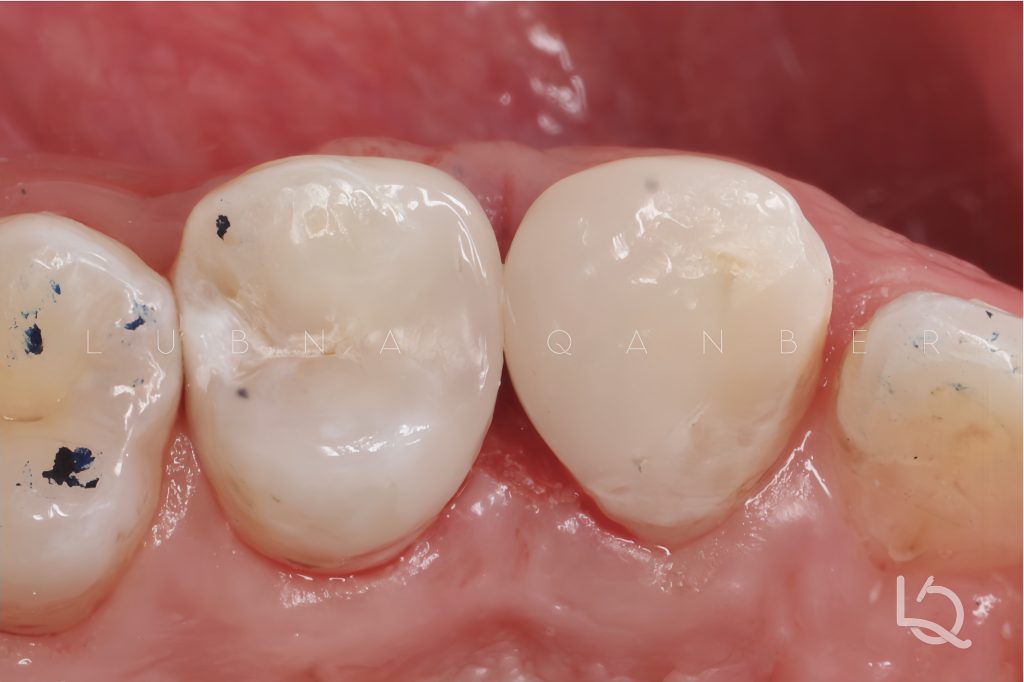

Final finishing and polishing were performed to achieve optimal anatomy and surface texture.

The final radiograph demonstrates a seamless, “infinite” margin on the mesial surface of the premolar and a well-integrated restoration of the canine, with harmonious contours and tight proximal contact.